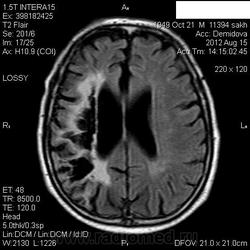

Мои собственные наблюдения.

1 случай -локальная гемиатрофия.2 случай-диффузная.

Молодой человек после автомобильной аварии.3 года лежит.Двигаются только глаза.Зрелище душещипательное.

Евгений, конечно же, мои случаи не являются "чистой" атрофией-согласна.Мне пока не встречались случаи болезни Пика, Альцгеймера и другие "чистой воды" атрофии.Второй случай- состояние после длительной комы вследствие автодорожной травмы 3 года назад.Пациент проходил исследование в прошлом году , в этом родители привезли на динамику.